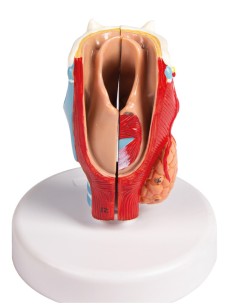

3B Scientific, modello anatomico funzionale di laringe: W42503